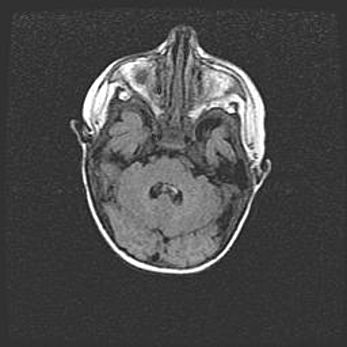

Церебральная ишемия II.

Возраст: 5 дней

Вес: 3400 г

Пол: женский

Окружность головы: 35 см

Срок гестации: 39 недель

Церебральная ишемия – это заболевание, характеризующееся недостаточностью (гипоксией) либо полным прекращением (аноксией) снабжения мозга кислородом по причине закупорки одного или нескольких сосудов. Это приводит к  что метаболическим расстройствам различной степени тяжести в тканях головного мозга, развитию коагуляционных некрозов и гибели нейронов.